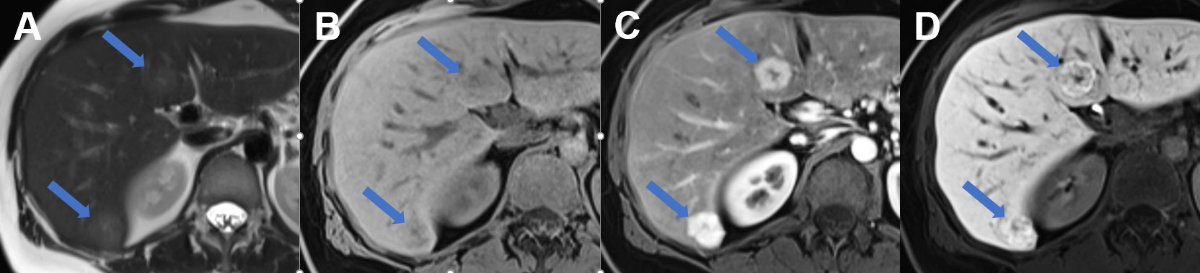

Figure 4Regional fatty sparing and focal steatosis on MRI. A MRI T1 weighted image of a case with focal sparing (arrow) of steatosis in the porta hepatis with B signal drop in the remaining liver on opposed phase images and persisting high signal in the spared area. C On fat only images, the fatty liver shows signal with the spared area appearing dark, while on D the water only image, the spared area is brighter than the steatotic surrounding liver.